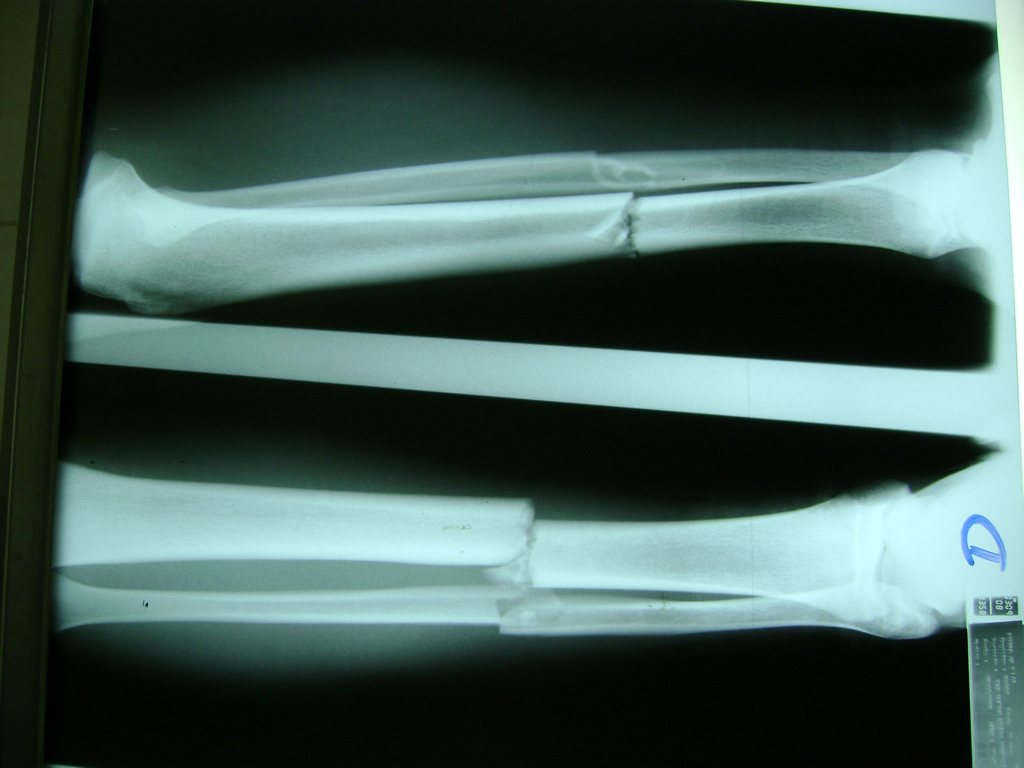

La mayor parte de las roturas implican a la parte proximal del hueso (parte del hueso próximo a la rodilla) o a la parte distal (parte del hueso cerca del tobillo).

Debido a la fina cobertura de piel que recubre la tibia y el peroné, las fracturas generalmente son abiertas, es decir, el hueso roto rasga la piel, atravesándola. Las fracturas de tibia y peroné generalmente se producen por un fuerte impacto o torsión.